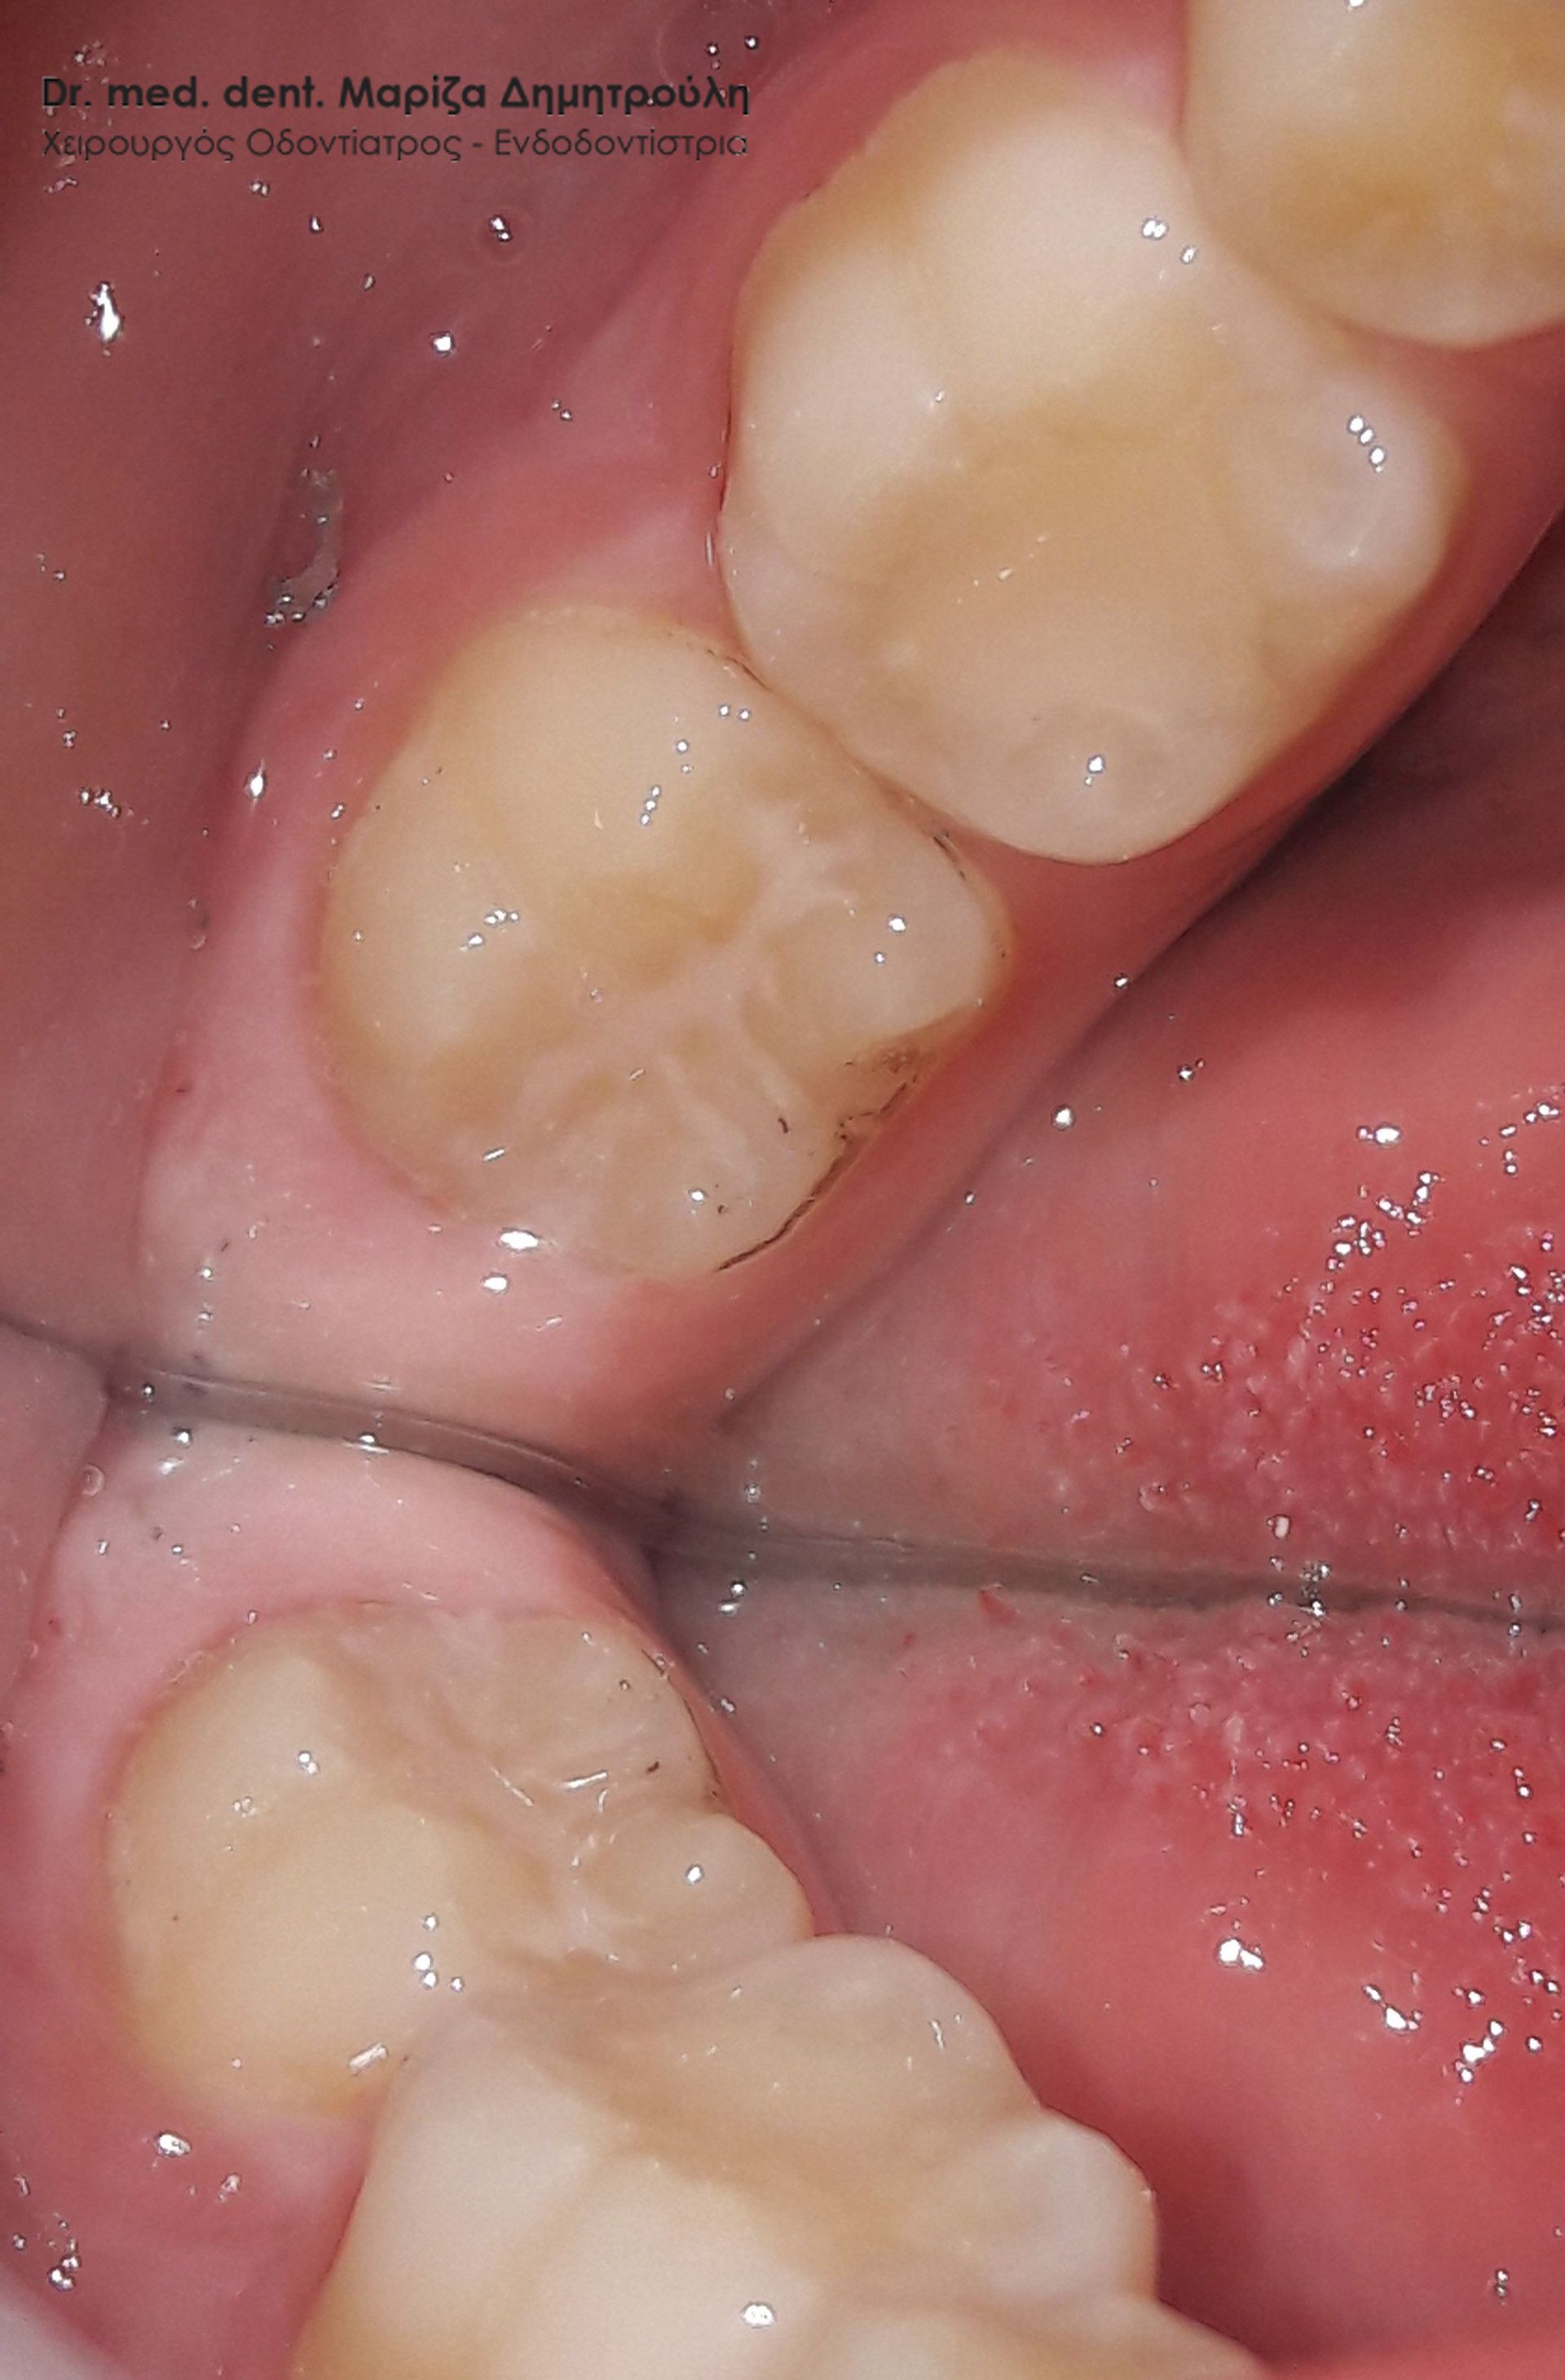

Στα πλαίσια του τυπικού οδοντιατρικού ελέγχου διαπιστώθηκε η ύπαρξη μιας μικρής τερηδονικής κοιλότητας στον πρώτο αριστερό μόνιμο γομφίο. Αποφασίστηκε η αφαίρεση της επιφανειακής αρχόμενης τερηδόνας και προληπτική κάλυψη οπών και σχισμών (sealant) στη μασητική επιφάνεια του μόνιμου άνω αριστερού πρώτου γομφίου.

Περιστατικά – Sealant / προληπτική κάλυψη οπών και σχισμών

Στο συγκεκριμένο ασθενή πραγματοποιήθηκε ταυτόχρονα αφαίρεση της επιφανειακής αρχόμενης τερηδόνας και προληπτική κάλυψη οπών και σχισμών (sealant) στη μασητική επιφάνεια του άνω αριστερού πρώτου γομφίου.